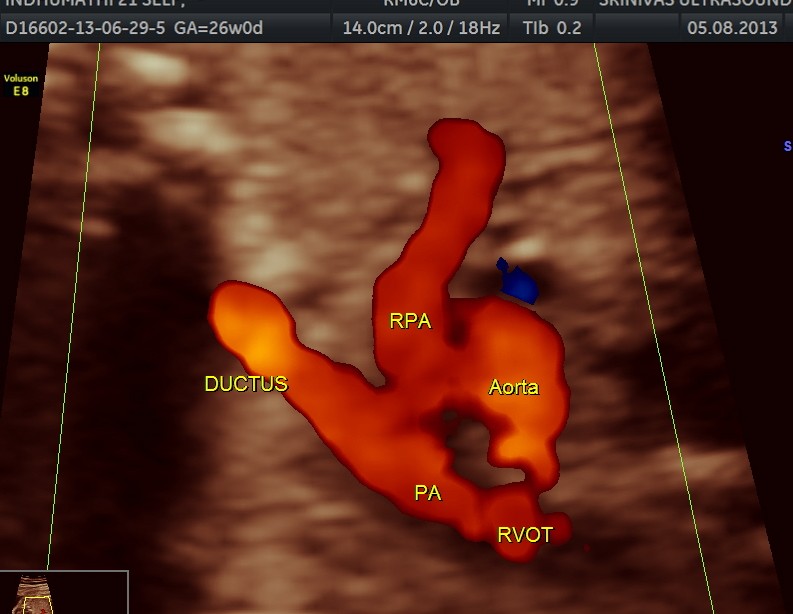

The following are of the 26 weeks gestation.